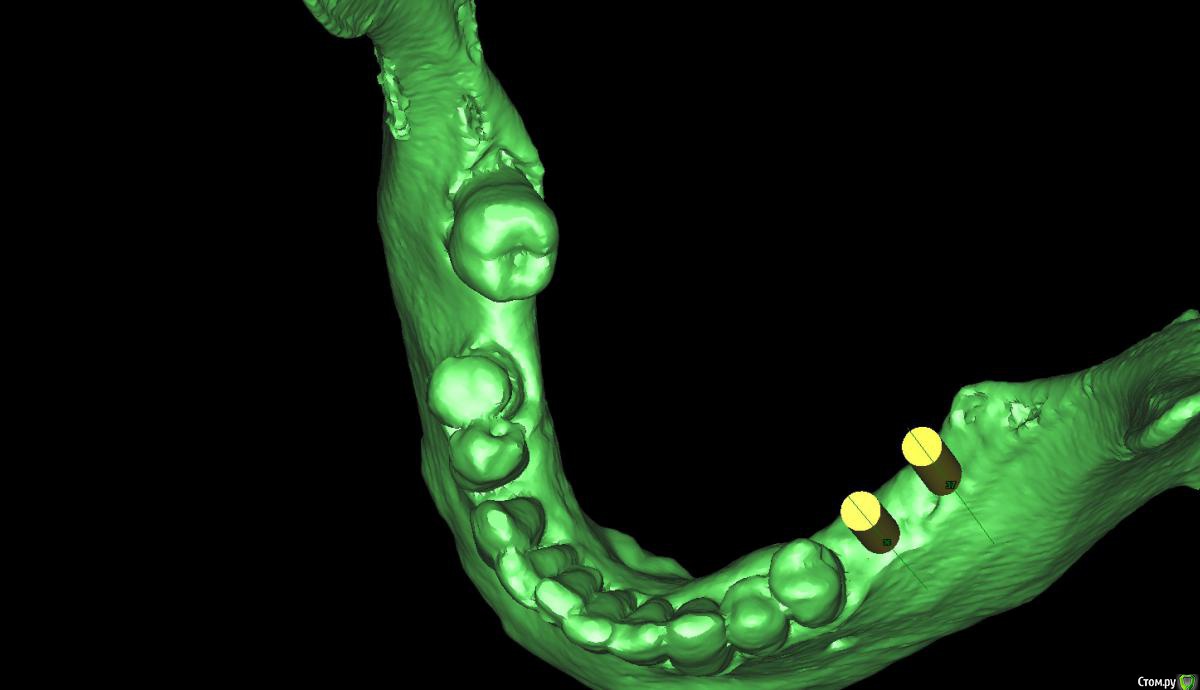

x4ex Опубликовано 8 сентября, 2017 Поделиться Опубликовано 8 сентября, 2017 Добрый день, коллеги! Планируется удаление 45 с последующей имплантацией. Но также нужно медиализировать 44 и дистализировать 47. Чем можно выполнить данное задание? Подойдёт ли EZSpacer? Есть ли другие аппараты для данных целей? Ссылка на комментарий

Ibulat_1986 Опубликовано 18 сентября, 2017 Поделиться Опубликовано 18 сентября, 2017 вокруг 45 кратеообразный дефект - перемещать его лучше ортодонтически, в идеале подключить имплантат через временную коронку Ссылка на комментарий